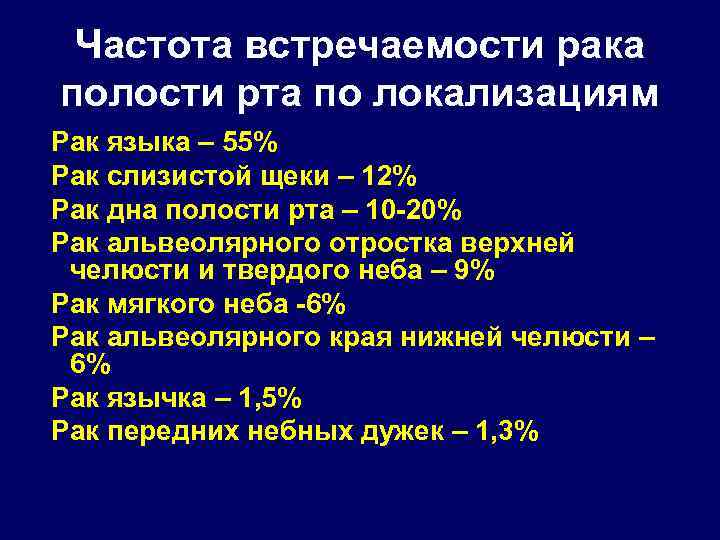

Частота встречаемости рака полости рта по локализациям Рак языка – 55% Рак слизистой щеки – 12% Рак дна полости рта – 10 -20% Рак альвеолярного отростка верхней челюсти и твердого неба – 9% Рак мягкого неба -6% Рак альвеолярного края нижней челюсти – 6% Рак язычка – 1, 5% Рак передних небных дужек – 1, 3%

Частота встречаемости рака полости рта по локализациям Рак языка – 55% Рак слизистой щеки – 12% Рак дна полости рта – 10 -20% Рак альвеолярного отростка верхней челюсти и твердого неба – 9% Рак мягкого неба -6% Рак альвеолярного края нижней челюсти – 6% Рак язычка – 1, 5% Рак передних небных дужек – 1, 3%